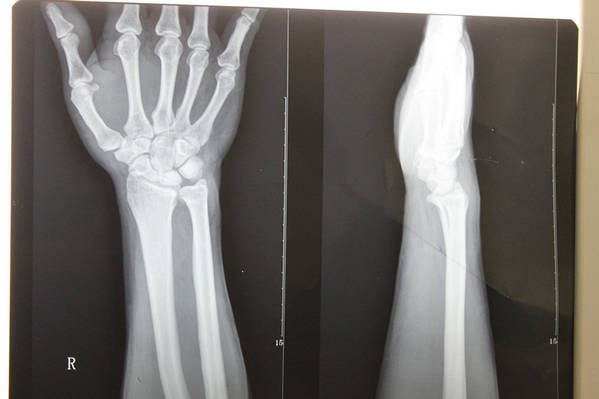

[手部疾病] 月骨缺血性坏死

患者  36岁  无外伤性腕关节疼痛,